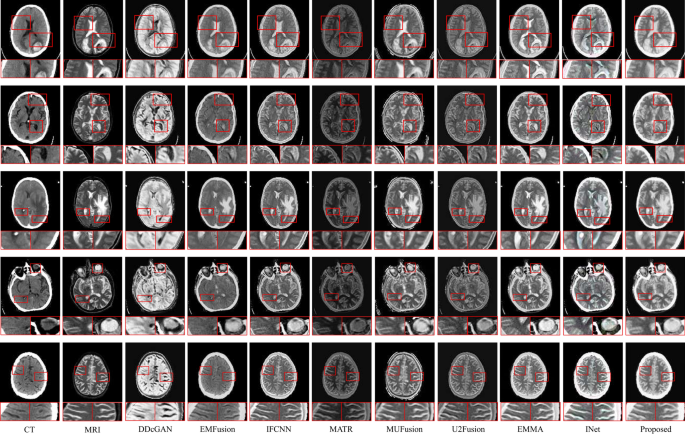

The experimental results of our proposed S3IMFusion on the Harvard dataset are shown in Fig. 3.

Results of CT and MRI image fusion on Harvard.

To provide a more detailed and illustrative evaluation, we select two local regions (indicated by red-boxed areas) for zoomed-in visual comparisons of the fused images. Each of the compared methods exhibits distinct strengths and limitations. The DDcGAN method enhances the brightness of fused images; however, it introduces significant artifacts, leading to pronounced blurring and reduced structural integrity. EMFusion effectively integrates salient features from CT images into the fused outputs, though at the cost of losing texture details from MRI images. A similar compromise is observed in the IFCNN method. MATR demonstrates a notable ability to combine detailed texture information and salient features, yet suffers from visible blurring and reduced brightness in the fused images, particularly in the CT-MRI fusion context. MUFusion introduces undesirable noise artifacts, severely compromising the visual quality of the fusion results. U2Fusion excels at incorporating intricate details from MRI images into the fused outputs but neglects critical complementary information from CT images, resulting in a loss of balance between modalities. EMMA effectively preserves the salient features of the original image; however, the fusion result suffers from a lack of fine-grained detail, leading to insufficient representation of intricate information. INet achieves a more complete preservation of the mutual information from the original image in the fused output, owing to the reversibility of the network, which effectively mitigates information loss. Nevertheless, this approach is plagued by the issue of color distortion. In contrast, the proposed S3IMFusion method demonstrates superior performance by effectively preserving salient features from CT images while maintaining the intricate texture details from MRI images. Moreover, it achieves an optimal balance between brightness and detail preservation, resulting in fused images with enhanced visual clarity and overall quality. This capability underscores the robustness and effectiveness of S3IMFusion in handling multi-modal medical image fusion tasks.

Table 1 presents the evaluation results derived from the eight metrics mentioned earlier. This evaluation is conducted using 21 pairs of CT and MRI images. For each metric, the final score is calculated by averaging the assessment scores of the 21 test samples. From Table 1, it can be seen that the proposed S3IMFusion method performs well in EN, AG and MI. INet achieves excellent results on SSIM, Qabf and SCD metrics, due to the information lossless extraction capability of the invertible network, which allows it to retain more structural information in the image. S3IMFusion also demonstrates relatively sub-optimal results in metrics such as PSNR and SSIM. Both U2Fusion and MUFusion demonstrate superior performance in terms of PSNR and SF metrics. The comprehensive analysis underscores the stability of S3IMFusion in producing fused images and its capability to achieve higher-quality outputs by effectively integrating both global and local features from the source images.